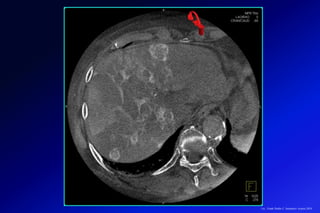

Paciente de 55 años con síndrome metabólico y aumento de enzimas hepáticas de causa no aclarada. (A y B) Secuencias de

desplazamiento químico que muestran una caída de la señal en la secuencia en fase opuesta, por esteatosis. (C) Secuencia

DIXON (IDEAL-IQ), que muestra una proporción de lípidos de 15% comparado con la del bazo (<5%), por esteatosis

moderada/severa. (D) ERM con marcado aumento en la rigidez del tejido hepático (8,2Kpa), hallazgos compatibles con una

esteatohepatítis no alcohólica (EHNA) asociada a fibrosis avanzada (F4).